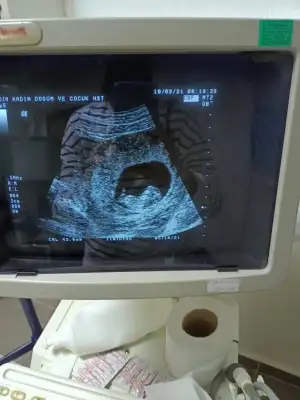

Merhaba kardeşinizin bebeğinin cinsiyeti belli oldumu?Teşekkürler erkek demiştiniz o haftalarda bugün gittiler doktora doktor kardeşime söylemedi eltisine söylemiş sürpriz olacak cinsiyet partisi yapacaklarmış cumabizimkise sabırsız meraktan soruyoz

Merhaba kızdır bebekMerhaba kardeşinizin bebeğinin cinsiyeti belli oldumu?![]()

Evet sonra bir USG paylaştı kız dedimMerhaba kardeşinizin bebeğinin cinsiyeti belli oldumu?![]()